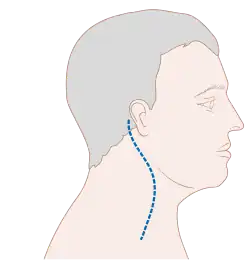

Spread of cancer from the oral cavity to the lymph nodes of the neck has a significant effect on survival. Between 60 and 70% of people with early stage oral cancer will have no lymph node involvement of the neck clinically, but 20–30% of those people (or up to 20% of all those affected) will have clinically undetectable spread of cancer to the lymph nodes of the neck (called occult disease).

The management of the neck is crucial, since spread to it reduces the chance of survival by 50%.[55] If there is evidence of lymph node involvement of the neck, during the diagnostic phase, then a modified radical neck dissection is generally performed. Where the neck lymph nodes have no evidence of involvement clinically, but the oral cavity lesion is high risk for spread (e.g. T2 or above lesions), then a neck dissection of the lymph nodes above the level of the omohyoid muscle may be completed. T1 lesions that are 4 mm or greater in thickness have a significant risk of spread to neck nodes. When disease if found in the nodes after removal (but not seen clinically) the recurrence rates is 10–24%. If post-operative radiation is added, the failure rate is 0–15%. When lymph nodes are clinically found during the diagnosis phase, and radiation is added post-operative, disease control is >80%.[56]